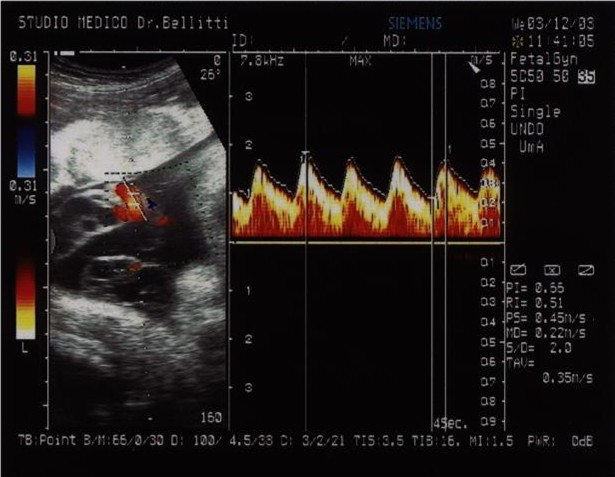

LEA, Livelli Essenziali di Assistenza, Curriculum Vitae, Padova, Vicenza, Venezia, Rovigo, Belluno, Verona, Treviso, Veneto, Harmony Test, ARIOSA, PrenatalSafe, Prenatal Safe, GENOMA, Vera Prenatal Test, Ecografia Tridimensionale, Ecografia Tridimensionale a Padova, Ecografia Tridimensionale a Vicenza, Test Combinato, Test Combinato a Padova, Test Combinato a Vicenza, Ultrascreen, Ultrascreen a Padova, Ultrascreen a Vicenza, Harmony Test, Harmony Test a Padova, Harmony Test a Vicenza, Ecografia 3D, Ecografia 3D a Padova, Ecografia 3D a Vicenza, Ecografia morfologica, Ecografia morfologica a Padova, Ecografia morfologica a Vicenza, Ecografia di I° livello, Ecografia di II° livello, Ecografia di 1° livello, Ecografia di 2° livello, Ecografia ostetrica, Ecografia ostetrica a Padova, Ecografia ostetrica a Vicenza, Ecografia in gravidanza, Ecografia in gravidanza a Padova, Bellitti Francesco Ginecologo, Ecografia in gravidanza a Vicenza, Ecografia 3 D, Ecografia 3 D a Padova, Ecografia 3 D a Vicenza, Ricerca DNA Fetale, Ricerca DNA Fetale a Padova, Ricerca DNA Fetale a Vicenza, Ecografia genetica, Ecografia genetica a Padova, Ecografia genetica Vicenza, Ecografista Accreditato, Ecografista Accreditato a Padova, Ecografista Accreditato a Vicenza, Ecografisti Accreditati, Ecografisti Accreditati a Padova, Ecografisti Accreditati a Vicenza, Bi-test, bi-test a Padova, bi-test a Vicenza, Osso nasale, osso nasale a Padova, osso nasale a Vicenza, Ostetricia, ostetricia Padova, ostetricia Vicenza, Ginecologia, ginecologia Padova, ginecologia Vicenza, Villocentesi, Villocentesi a Padova, Villocentesi a Vicenza, Amniocentesi, Amniocentesi a Padova, Amniocentesi a Vicenza, Ecografia ginecologica, Ecografia ginecologica a Padova, Ecografia ginecologica a Vicenza, Screening per la sindrome di Down, Screening per la sindrome di Down a Padova, Screening per la sindrome di Down a Vicenza, Test Harmony, Test Harmony a Padova, Test Harmony a Vicenza, Bitest, bitest a padova, bitest a Vicenza, Bi test, bi test a padova, bi test a Vicenza, 3D, 3D a Padova, 3D a Vicenza, 3 D, 3 D a Padova, 3 D a Vicenza, 4D, 4D a Padova, 4D a Vicenza, Ecografia 4D, Ecografia 4D a Padova, Ecografia 4D a Vicenza, 4 D, 4 D a padova, 4 D a Vicenza, Ecografia 4 D, Ecografia 4 D a Padova, Ecografia 4 D a Vicenza, Padova, Vicenza, Venezia, Rovigo, Belluno, Verona, Treviso, Veneto È opinione diffusa che basta fare una ecografia nel 5º mese di gravidanza, la cosiddetta ecografia “morfologica”, per essere certi che nascerà un bambino “sano”, ma formulare la prognosi di una gravidanza e del relativo parto ed esito neonatale rimane la più grande sfida della medicina materno-fetale. Le patologie fetali sommariamente possono essere distinte in 5 gruppi: malformazioni, malattie geniche, anomalie cromosomiche, infezioni fetali, danno cerebrale ipossico. Le Malformazioni sono difetti anatomici di un organo o di un sistema di organi che derivano da un’alterato sviluppo dell’organo fetale durante la morfogenesi. Nella maggior parte dei casi non è possibile risalire alla causa dell'anomalia; in altri casi, invece, la causa della malformazione è riconducibile ad anomalie cromosomiche, malattie geniche, assunzione di farmaci, infezioni fetali, malattie materne, etc. Tali condizioni possono indurre Teratogenesi (malformazioni per esposizione durante l’organogenesi) o Mutagenesi (mosaicismo somatico localizzato che può esprimersi nella vita futura o nelle generazioni successive). Un feto ogni 40 è affetto da una malformazione. Fra le malformazioni più frequenti vi sono: il labbro leporino, l’idrocefalia, la spina bifida, l'atresia esofagea, l’ernia diaframmatica, la gastroschisi, l'onfalocele, etc. Purtroppo la diagnosi prenatale delle malformazioni è molto difficile e in alcuni casi impossibile; pertanto talvolta è tardiva (IIIº trimestre di gestazione) o non viene fatta. Le Anomalie Cromosomiche sono alterazioni del numero (aneuploidie) o della struttura (anomalie strutturali) dei cromosomi. Il corredo cromosomico umano è costituito da 46 cromosomi (23 coppie): 44 autosomi e 2 gonosomi (cromosomi sessuali), 23 di origine paterna e 23 di origine materna. Le anomalie riguardanti il numero sono le monosomie, le triploidie, e le poliploidie, mentre quelle riguardanti la struttura sono le delezioni, le traslocazioni e le inversioni. Le anomalie possono essere in linea pura, cioè presenti in tutte le cellule dell’individuo o in mosaico, cioè solo in una certa percentuale di cellule. Le trisomie, nelle quali è presente un cromosoma soprannumerario non sono trasmesse ereditariamente, ma insorgono casualmente a causa della non disgiunzione cromosomica, spesso legata all’età materna. Le anomalie strutturali, quali delezioni e traslocazioni, sono molto più rare, ma possono essere trasmesse da uno dei genitori che ne sia portatore. Circa un feto ogni 100 ha una anomalia cromosomica grave. In linea di massima le anomalie cromosomiche possono determinare danni a livello fisico, mentale e psico-motorio. Fra le anomalie cromosomiche vi sono la Trisomia 21 (o Sindrome di Down), la Trisomia 18 (o Sindrome di Edwards), la Trisomia 13 (o Sindrome di Patau), la Monosomia X (o Sindrome di Turner), la Sindrome di Klinefelter, etc. Purtroppo per moltissime anomalie cromosomiche la diagnosi prenatale non fornisce un’indicazione sicura al 100%, ma la risposta può essere espressa sotto forma di probabilità percentuale o riferita a casi analoghi riportati dalla letteratura medica. Spesso la stessa anomalia può provocare problematiche più o meno gravi ed avere effetti molto diversi da un individuo all’altro, cosicchè la prognosi risulta molto difficile. Le Malattie Geniche sono causate dall’alterazione di una base azotata su 3.000.000.000 di sequenze di basi azotate che formano i circa 100.000 geni che costituiscono il DNA di cui sono composti i cromosomi. Le malattie geniche conosciute sono oltre 7000; attualmente, però, solo una parte di queste (circa 300) sono diagnosticabili in epoca prenatale e solo in alcuni laboratori di genetica e diagnosi molecolare, e non vengono ricercate con le villocentesi o le amniocentesi di routine. Per ricercare le malattie geniche nel DNA fetale è necessaria una specifica e preventiva richiesta al genetista (es. se i genitori sono portatori di una malattia genica conosciuta). Circa il 3% dei nati ha una malattia genica. A seconda dell’estrinsecazione della malattia, le malattie geniche sono suddivise in malattie autosomiche recessive, autosomiche dominanti o legate al cromosoma X (X-linked). Fra le Malattie geniche ci sono la Fibrosi cistica, la Talassemia, l’Anemia falciforme, la Sindrome Adrenogenitale, l’Osteogenesi imperfetta tipo Iº, la Sindrome di Marfan, la Distrofia Miotonica, la Chorea di Huntington, la Distrofia muscolare di Duchenne, l’Emofilia, la Sindrome dell’X Fragile, etc. Alcune anomalie possono presentarsi in forma più o meno grave, oppure avere un’età di esordio variabile, ma non è possibile prevedere né l’età di esordio né se il nascituro svilupperà la malattia in forma lieve o grave. L’ecografia è una tecnica che utilizza ultrasuoni (onde sonore ad alta frequenza), che in parte attraversano i tessuti ed in parte vengono riflessi (eco) e trasformati in immagini nel monitor dell’ecografo, consentendo di osservare il feto dentro l’utero; con le procedure oggi adottate, l’uso diagnostico dell’ecografia è ritenuto esente da rischi sia per la madre che per il feto. L’Ecografia fetale consente sia una valutazione morfologica e biometrica del feto (diagnosi delle malformazioni e valutazione della crescita), sia una valutazione dello stato di benessere fetale e della riserva funzionale. Sono stati riportati, inoltre, alcuni reperti ecografici potenzialmente utili per “sospettare ecograficamente” feti affetti da anomalie cromosomiche (come la Sindrome di Down o Trisomia 21, causata da un cromosoma 21 sovrannumerario trasmesso all'embrione dalla madre): due di queste tipiche stigmate predittive per anomalie cromosomiche sono l'assenza dell'Osso Nasale (non visualizzabile nel 60-70% dei feti affetti dalla Sindrome di Down) e l'aumentato spessore della Translucenza Nucale (cioè lo spessore cutaneo nucale). La possibilità di rilevare un'anomalia maggiore dipende dalla sua dimensione, dall'epoca di gravidanza, dalla posizione del feto, dalla quantità di liquido amniotico, dallo spessore della parete addominale materna; perciò e per i limiti intrinseci della metodica, è possibile che alcune anomalie, anche importanti, non siano rilevate. In alcuni casi può essere necessario eseguire l’esame con la sonda ecografica endovaginale, inoltre, può essere necessario ripetere l'esame più volte o sottoporsi ad approfondimenti diagnostici specifici e mirati. Un reperto di “normalità” non esclude la possibilità che il bambino presenti una malformazione o una anomalia cromosomica (falso negativo), così come un reperto “anomalo” può essere rinvenuto in un feto sano (falso positivo). Un reperto di “normalità” non esclude la possibilità che il bambino presenti ritardo mentale, cecità, sordità ed altri difetti sensoriali e/o motori. Le anomalie congenite sono presenti nel 2.5-3% delle gravidanze (circa un feto su 40), in particolare le anomalie cromosomiche sono presenti nell’1% circa delle gravidanze. L’ecografia “morfologica” (consigliata alla 19ª-21ª settimana gestazionale) permette di escludere la maggior parte delle malformazioni maggiori, mentre altre anomalie, anche importanti, a causa delle ridotte dimensioni o delle modalità di evoluzione, è possibile che siano evidenziate tardivamente o non siano rilevate (alcune malformazioni cardiache, del sistema nervoso centrale, del tubo digerente, del sistema urinario, emorragie, cisti, tumori, etc.). Non è compito dell’ecografia la rilevazione delle cosiddette anomalie minori. Con l'ecografia non è possibile diagnosticare le anomalie genetiche, sia geniche (fibrosi cistica, talassemia, etc.), sia cromosomiche (come la Sindrome di Down). Un esame ecografico routinario (Iº livello) consente di identificare dal 30% al 70% delle malformazioni fetali maggiori, mentre una ecografia eseguita da un operatore particolarmente esperto (IIº livello) può incrementare il tasso di diagnosi fino al 90%. Le ecografie fatte nel corso della gravidanza sono complementari e sono ognuna un completamento della precedente, pertanto la difficoltà di escludere le anomalie fetali diventa ancora maggiore se il medico effettua una sola ecografia in tutta la gravidanza, in quanto la morfogenesi fetale è un evento evolutivo che non può essere colto in maniera omnicomprensiva con un unico esame ecografico. Non è un obiettivo dell’ecografia del secondo trimestre lo screening delle anomalie cromosomiche mediante la ricerca dei marcatori ecografici di cromosomopatia. Nel caso in cui venga riscontrata una anomalia fetale si consiglia di eseguire una ecografia presso un Centro di IIº livello e, in alcuni casi, lo studio del cariotipo fetale (mappa cromosomica), per accertare o escludere la presenza di anomalie cromosomiche, mediante Villocentesi, Amniocentesi. La legge 194/1978, che regolamenta l’interruzione volontaria della gravidanza, consente di interrompere la gravidanza entro il 180º giorno dal suo inizio (aborto terapeutico). Purtroppo la “vitalità” è difficile da definire a priori, quindi, in una percentuale limitata, ma non irrilevante, di casi il feto, una volta espulso, potrebbe sopravvivere, in quanto la sopravvivenza è possibile anche entro il 180º giorno. Il Profilo Biofisico Fetale Ecografico è un metodo per la valutazione del benessere fetale basato sulla sorveglianza di 4 variabili biofisiche fetali: movimenti corporei. movimenti respiratori, tono muscolare e quantità di liquido amniotico. Le prime 3 variabili sono regolate da centri nervosi, pertanto riflettono lo stato del Sistema Nervoso Centrale, mentre la quantità di liquido amniotico riflette la riserva funzionale del feto e fornisce, indirettamente, una al stima del compenso emodinamico. La Velocimetria Doppler è una metodica ecografica per mezzo della quale è possibile misurare la velocità del sangue nei vasi sanguigni della circolazione materna e feto-placentare e rilevare le variazioni di flusso tipiche della sofferenza fetale, che talvolta precedono di qualche settimana i segni biofisici della sofferenza stessa. Sia il Profilo Biofisico Fetale che la Velocimetria Doppler permettono, talvolta, la diagnosi precoce della sofferenza fetale quando, grazie ai meccanismi omeostatici del feto, non è ancora avvenuto il danno neurologico; ciò è importante per attuare una corretta condotta ostetrica al fine di prevenire il danno cerebrale feto-neonatale e ridurre l’incidenza di handicaps. Una delle più comuni cause di handicap è la sindrome di Down, causata da un cromosoma 21 sovrannumerario trasmesso all'embrione dalla madre (Trisomia 21). La possibilità di procreare un figlio affetto dalla sindrome di Down, seppur in percentuale diversa, è presente per le donne di tutte le età (vedi tabella).

La Translucenza Nucale (T.N.) è lo spessore dei tessuti molli a livello della nuca fetale; uno spessore di 3 millimetri, o più, della Translucenza Nucale indica un rischio aumentato di circa 10 volte, rispetto a quello atteso per l’età materna, che il feto sia affetto da Sindrome di Down, e può portare ad identificare i feti affetti da Sindrome di Down nel 75% dei casi, con tasso di falsi positivi del 5% (percentuale di individui sani con test "patologico"); la misurazione della translucenza nucale, eventualmente associata alla ricerca dell’Osso Nasale Fetale, sono usate come tests di screening prenatale per la Sindrome di Down, la cui probabilità aumenta in caso di assenza dell’osso nasale. La misurazione della Translucenza Nucale e la ricerca dell’osso nasale si effettuano fra 11 settimane e 3 giorni e 13 settimane e 6 giorni di gestazione, ovvero se la misura cranio-caudale fetale è compresa fra 45 e 84 millimetri, secondo le linee guida della F.M.F. (Fetal Medicine Foundation di Londra), e la stima del rischio teorico che il feto sia affetto da Sindrome di Down è effettuata da un programma computerizzato che esegue una valutazione combinata dello spessore della Translucenza Nucale, della presenza/assenza dell’osso nasale fetale e dell’età materna, e può identificare circa il 90% dei feti affetti da Sindrome di Down. Nei casi in cui lo spessore della Translucenza Nucale risulta aumentato, in assenza di anomalie cromosomiche, potrebbe essere indice di alcune malformazioni (soprattutto cardiache), pertanto si raccomanda di eseguire una ecografia presso un Centro di IIº livello alla 19ª-21ª settimana gestazionale. Il Test Combinato consiste nel combinare l'età materna e la misurazione della Translucenza Nucale con un test biochimico, dosando 2 ormoni nel sangue materno (PAPP-A e free βeta-HCG); con questa combinazione si possono identificare circa l'85-90% dei feti affetti da Sindrome di Down, e questa percentuale arriva fino al 95% se si associa la ricerca dell'osso nasale. Il Triplo Test (o Tri-Test) è un test di screening prenatale sia per la Sindrome di Down che per i difettii del tubo neurale (come la spina bifida) e si effettua, solitamente, fra 15 settimane e 18 settimane e 6 giorni di gestazione, dosando 3 ormoni nel sangue materno: alfa-fetoproteina (α-FP), beta-gonadotropina corionica (β-HCG), ed estriolo non coniugato (uE3); i valori relativi di questi 3 ormoni vengono poi analizzati da un programma computerizzato che fornisce un rischio stimato sia per i difetti del Tubo Neurale che per la Sindrome di Down che consente di identificare nel 60% dei casi. Se oltre ai 3 ormoni sopracitati si dosa anche l'inibina A, il test viene chiamato Quadruplo Test e consente di identificare circa il 70% dei feti affetti da Sindrome di Down. Il Test Integrato è un test che prevede 2 fasi: misurazione della Translucenza Nucale e dosaggio della PAPP-A nel I° trimestre di gravidanza e Quadruplo Test nel II° trimestre; il risultato dello screening viene fornito solo dopo quest'ultimo test. Sommariamente si può dire che il Test integrato ha il vantaggio di avere un minor numero di falsi positivi (circa 1%), e lo svantaggio di avere il risultato nel II° trimestre. Tutti i tests sopradescritti sono tests di screening, cioè non permettono la diagnosi prenatale della Sindrome di Down e non sono sostitutivi delle indagini invasive (Villocentesi o Amniocentesi), ma servono ad individuare, fra le gravide con un basso rischio che il feto sia affetto da Sindrome di Down, quelle la cui probabilità risulta aumentata. Approssimativamente si può dire che con gli esami di screening per circa il 2% delle gravide si risconta un rischio che il feto sia affetto dalla sindrome di Down di 1 su 100 o più; le donne con un rischio compreso fra 1 su 101 e 1 su 1000 rappresentano circa il 16%, mentre nell'82% delle gravide si riscontra un rischio inferiore a 1 su 1000. Il punto debole dei tests di screening sono sia i falsi negativi (feti affetti con test "non patologico") per i quali, purtroppo, non saranno consigliate indagini invasive, sia i falsi positivi (feti sani con test "patologico"), ai quali, purtroppo, sarà consigliata una indagine invasiva, con un rischio di aborto per un feto cromosomicamente sano; attualmente, infatti, solo metodiche invasive come la Villocentesi e l’Amniocentesi danno una sicura diagnosi prenatale delle anomalie cromosomiche. La Fetal Medicine Foundation ha consigliato di eseguire una diagnosi prenatale invasiva (villocentesi o amniocentesi) qualora la probabilità che il feto fosse affetto da sindrome di Down risultasse 1:300 o maggiore; l’attuale orientamento, però, è quello di proporre la diagnosi prenatale invasiva alle gravide con un rischio di 1 su 100 o più, dato che in questa fascia di rischio vi sono circa l’80% dei feti affetti dalla sindrome di Down. Nella fascia di rischio compresa fra 1 su 101 e 1 su 1000 vi sono circa il 15% dei feti affetti dalla sindrome di Down, pertanto si consiglia di eseguire una ecografia fetale di II° livello già nel I° trimestre di gravidanza, e la diagnosi prenatale invasiva verrebbe proposta solo alle donne nei cui feti venisse riscontrata una alterazione del flusso ematico nel dotto venoso o un rigurgito di sangue attraverso la valvola cardiaca tricuspide. In questo modo si sottoporrebbe agli esami invasivi solo il 3% delle gravide, ma si individuerebbe circa il 90% dei feti affetti dalla sindrome di Down, riducendo drasticamente il numero degli aborti causati dalla diagnosi prenatale invasiva. Il Decreto del Ministro della Sanità del 10 settembre 1998, a tutt’oggi in vigore, pone, fra le indicazioni per le indagini per la diagnosi citogenetica prenatale delle anomalie cromosomiche (Villocentesi, Amniocentesi, etc), escluse dalla partecipazione al costo se fruite presso le strutture sanitarie pubbliche e private accreditate, la probabilità di 1:250, o maggiore, che il feto sia affetto da Sindrome di Down, sulla base di parametri ecografici o biochimici valutati su sangue materno. La Ricerca del DNA Fetale nel Sangue Materno, chiamato anche NIPT cioè Non Invasive Prenatal Testing (HARMONY TEST, PRENATALSAFE, VERA TEST, etc), è un TEST NON INVASIVO (senza rischi sia per la madre che per il feto) che utilizza una tecnologia che permette, con un semplice prelievo di sangue materno, di analizzare frammenti di DNA di origine fetale specifici dei cromosomi 21, 18, 13, X e Y e di definire, con un alto grado di accuratezza, se il feto è ad alto o basso rischio per le Trisomie, cioè anomalie cromosomiche dovute alla presenza di tre copie di un particolare cromosoma invece delle due previste. Si tratta di un test di screening sviluppato e validato a livello scientifico. I risultati sono espressi in termini di probabilità, ma dagli studi scientifici effettuati il Test è in grado di identificare oltre il 99% dei casi di Trisomia 21 (Sindrome di Down), il 98% di quelli con Trisomia 18 e l’80% di quelli con Trisomia 13, con una percentuale di casi falsi positivi <0.1%. · Si esegue un semplice prelievo di sangue materno a partire dalla 10ª settimana di gestazione. · Si invia il campione presso i Laboratori. I risultati delle analisi saranno disponibili dopo circa 3-5 giorni dal prelievo.